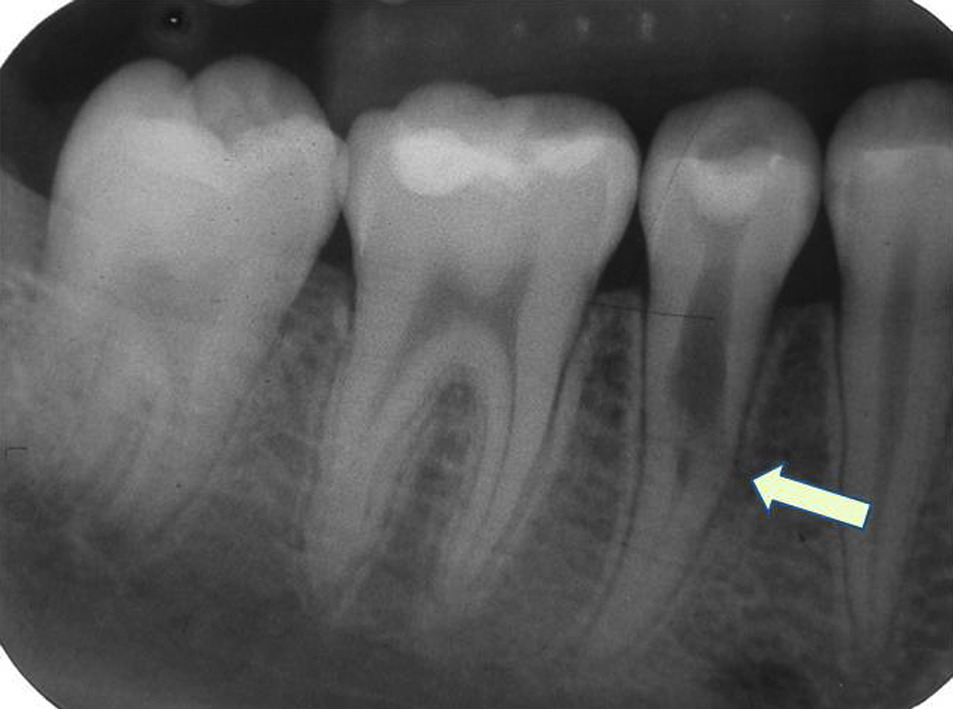

Diş için: Klinik muayene ve dental görüntüleme

Diş rezorpsiyonunda ilk adım detaylı klinik muayenedir. Dişin rengi, hassasiyeti, diş eti durumu ve travma/ortodonti öyküsü değerlendirilir. [17]

Çoğu olguda tanıyı destekleyen ana araç dental röntgen görüntüleridir. İki boyutlu görüntüler bazı lezyonları erken dönemde kaçırabilir; bu nedenle seçilmiş durumlarda üç boyutlu görüntüleme yöntemleri tanıyı netleştirmede yardımcı olabilir. [16] [17]

Eksternal rezorpsiyon ise dişin kök yüzeyinden veya servikal bölgeden başlar ve içe doğru ilerler. İltihabi uyarılar, travma, bazı ortodontik kuvvetler veya komşu dokulardaki patolojiler tetikleyici olabilir. [16] [17]

Eksternal rezorpsiyon tek bir tablo değildir; farklı mekanizmalarla ilerleyen alt tipleri vardır. Sınıflamalar değişebilse de klinikte en sık konuşulanlar; yüzey (geçici), inflamatuvar, replasman (ankilozla giden) ve servikal rezorpsiyondur. [1] [17]

- Servikal rezorpsiyon: Diş eti hizasına yakın servikal bölgede başlar ve erken dönemde belirti vermeden ilerleyebilir. [1]

| Görüntüleme ipucu | Pulpa kanalında simetrik genişleme | Kök yüzeyinde düzensiz madde kaybı, kontur bozulması |